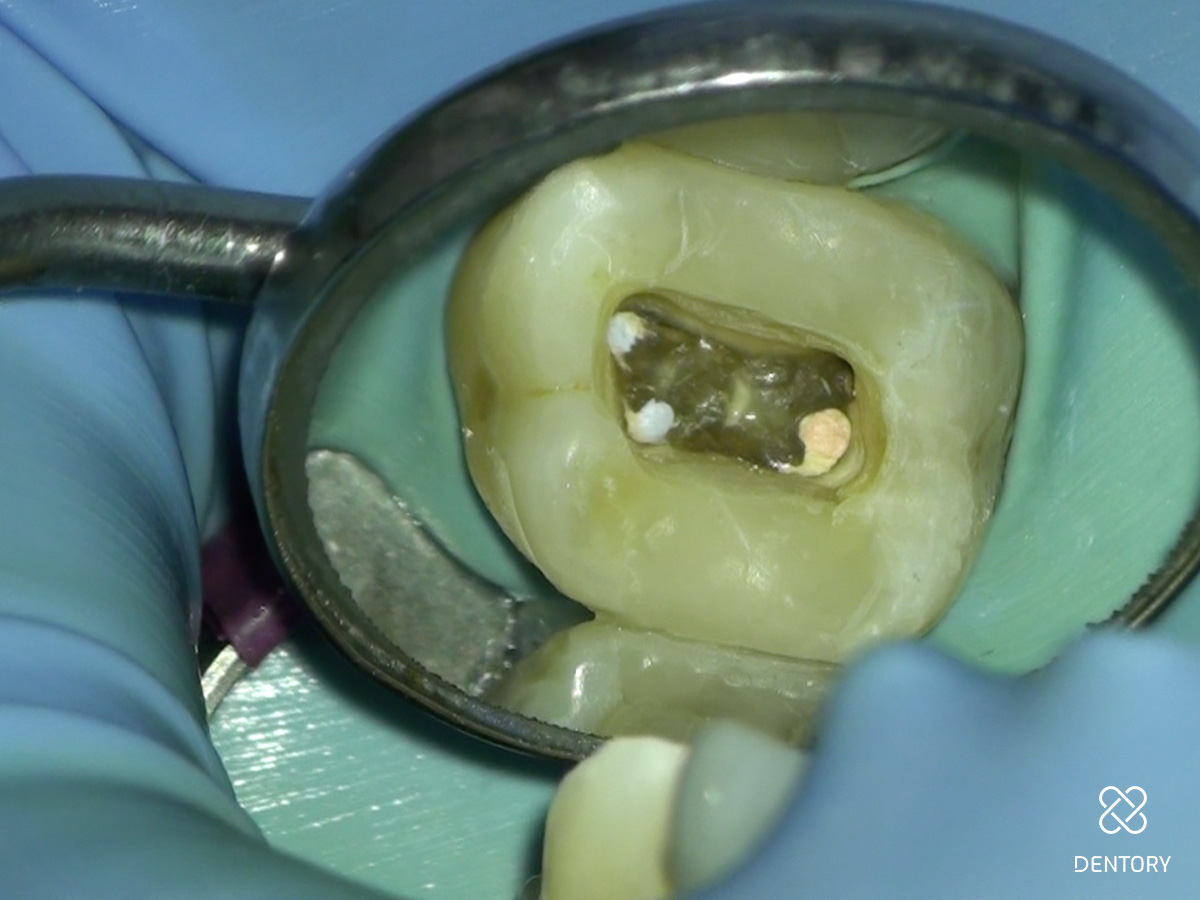

Abbildung 4

Aufbaufüllung: Versorgung des Zahnes mit einer dichten und stabilen Aufbaufüllung vor Beginn der Wurzelbehandlung. Am besten sind dafür adhäsiv befestigte Kompositfüllungen geeignet.